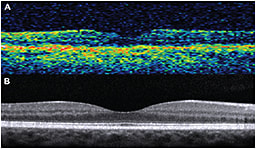

The first commercially available OCT systems were based on so-called time-domain technology. In time-domain OCT, a mechanical moving part performed the A-scan, and the information along the longitudinal direction accumulated over the course of the longitudinal scan time. These systems performed 400 axial scans per second and had an axial resolution of 8-10 µm (Figure 1A).

Figure 1. A) Time-domain OCT (Stratus OCT; Carl Zeiss Meditec, Dublin, CA); B) Spectral-domain OCT (Spectralis, Heidelberg Engineering, Carlsbad, CA).

In contrast, modern SD-OCT systems do not have mechanically moving parts but implement the mathematical principle of Fourier transformation, measuring all echoes of light simultaneously, compared with sequentially in the case of TD-OCT

As a result, SD-OCT can perform 100,000 to 250,000 axial scans per second, with an axial resolution of 1-5 µm (Figure 1B). SD-OCT has led to faster acquisition times, facilitating the implementation of real-time eye motion tracking and B-scan averaging.